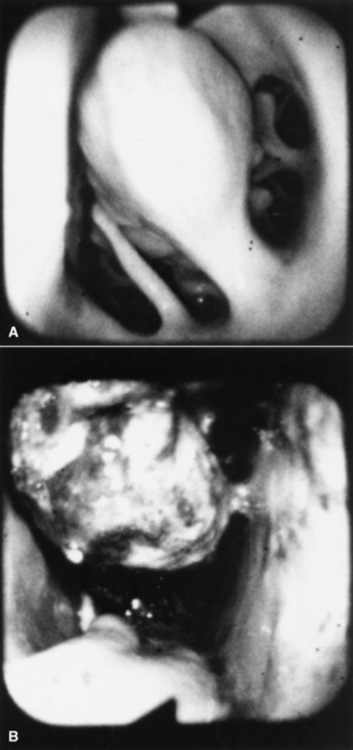

image

Fig. 31-46 Lateral radiograph demonstrating an ethmoid hematoma.

Recognition of a discrete, often smooth-surfaced homogeneous radiodensity originating from the ethmoidal conchae and extending into the frontal, maxillary, or sphenopalatine sinuses or into the pharynx or nasal cavity is suggestive of an ethmoid hematoma. Radiography is beneficial in determining the extent of the hematoma and in identifying suspected ethmoid hematomas that are not visible by endoscopy; however, precise definition of the origin of any hematoma is difficult from radiographic projections. Small hematomas contained within the ethmoid labyrinth may not be visible on radiographs. Computed tomographic examination of the skull allows more accurate assessment of the origin of the ethmoid hematoma,1207,1209 allows determination of the extent of involvement of the paranasal sinuses and conchae, and facilitates surgical planning.